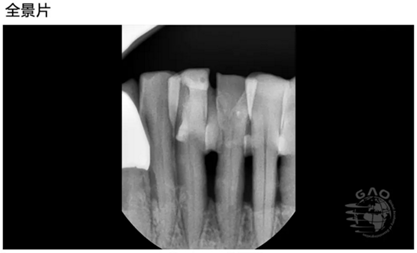

[臨床分享]使用取帽印模工具盒進(jìn)行下頜前牙區(qū)修復(fù) 科貿(mào)嘉友口腔收錄

- [臨床分享]使用取帽印模工具盒進(jìn)行下頜前牙區(qū)修復(fù) 科貿(mào)嘉友口腔收錄